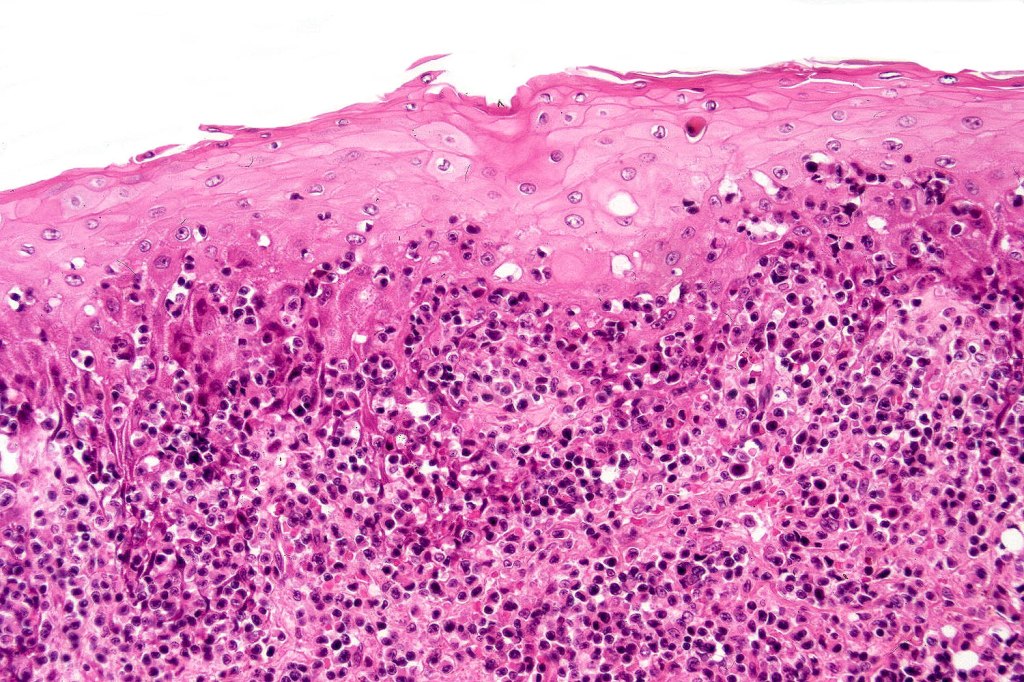

Histological features

The histological hallmark of mycosis fungoides is the presence of large atypical lymphocytes with a convoluted/cerebriform nuclear border (Sézary cells). These may be found at the epidermal-dermal jnuction and as collections within the epidermis (Pautrier microabscess). These are most easily found in plaque stage disease. The epidermal component can be subtle in patch stage disease and is often lost in tumor stage dsease. The classification into patch, plaque & tumor stage disease is less helpful histologically as the features merge from one to the other. It is all a matter of degree.

Tumor Stage Disease

•Epidermotropism is often minimal or absent

•Dense, broad diffuse or nodular, dermal infiltrate often extending into the subcutaneous fat

•Abundant Sézary cells. Frequently accompanied by very pleomorphic forms

•Mitoses often abundant, frequently abnormal

•CD30 expression correlates with transformation (cells X4 size of small lymphocytes comprising 25% or more of the infiltrate or the presence of a distinct large nodule)